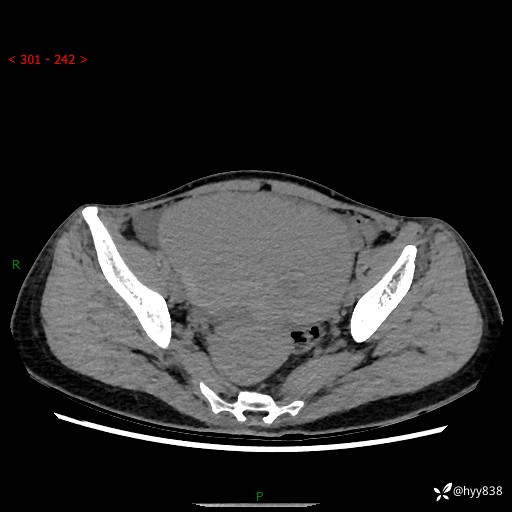

【患者信息】:女,50岁

【主诉】:外院超声发现腹盆肿块,为进一步诊治来我院,门诊已“盆腔肿块”收入院。

腹盆CT平扫+增强

【临床诊断】:盆腔肿瘤